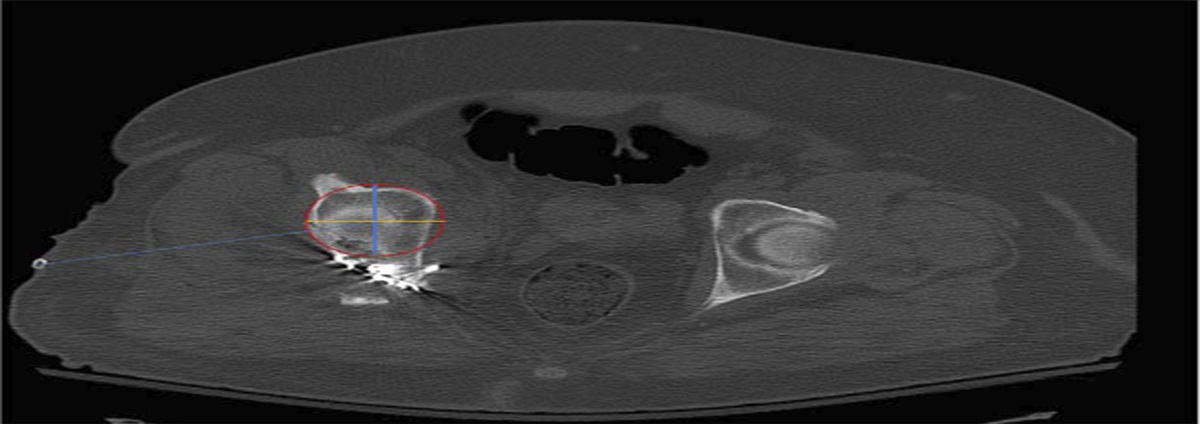

To determine whether muscle-to-adipose ratio (MAR) along the course of a Kocher-Langenbeck incision is more accurate at predicting postoperative wound complications after acetabular fixation than waist-to-hip ratio or body mass index (BMI).

Presence of a surgical site infection or a wound healing complication. BMI, WHR and MAR were evaluated and compared for their ability to predict a surgical site infection or a wound healing complication.

One-hundred ninety-three patients were included in this study, and the mean follow-up was 17.4 months. Thirty patients (15.5%) developed a wound complication. Seventeen patients (8.8%) developed a superficial infection and 13 (6.7%) developed a deep infection. The mean BMI for those who developed a wound complication was 35.9. The mean MAR was 0.67 for patients who developed a wound complication versus 0.75 for those who did not. Receiver operator characteristic analysis showed an area under curve for BMI to be 0.717 (95% confidence interval [CI] 0.577–0.857, P = 0.006) and for MAR to be 0.680 (inverted, 95% CI, 0.507–0.854, P = 0.022). The area under curve for waist-to-hip ratio was not statistically significant.